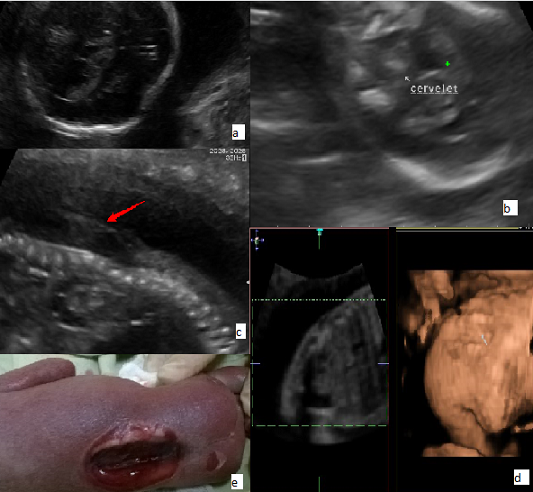

Il s’agit d’une patiente âgée de 30 ans, G1P0, adressée à notre unité de diagnostic anténatal pour suspicion de spina bifida aperta à un terme de 24 SA+2jr. L’échographie du premier trimestre réévaluée ne répondait aux critères qualités permettant de faire un diagnostic précoce. Les marqueurs sériques du premier trimestre prescrits, n’ont pas été réalisés par la patiente. L’échographie morphologique retrouve un diamètre bipariétal inférieur au 3ème percentile avec une dépression des os temporaux (A), une absence de visualisation de la grande citerne, un Chiari II avec un cervelet plongeant dans la fosse postérieure B) et une anomalie de fermeture du tube neural à type de rachischisis (C). Une échographie en mode tridimensionnelle a été réalisée visualisant le défect dorsolombaire étendu (D), mais persistance de mouvements des membres inférieurs jugés satisfaisants. Après informations délivrées au couple sur le pronostic sombre des anomalies échographiques constatées, le couple a décidé d’interrompre la grossesse E) après réalisation d’un caryotype sur liquide amniotique. La formule chromosomique était normale: 46, XY. A la sortie, une ordonnance de supplémentation en acide folique a été délivrée à la patiente.